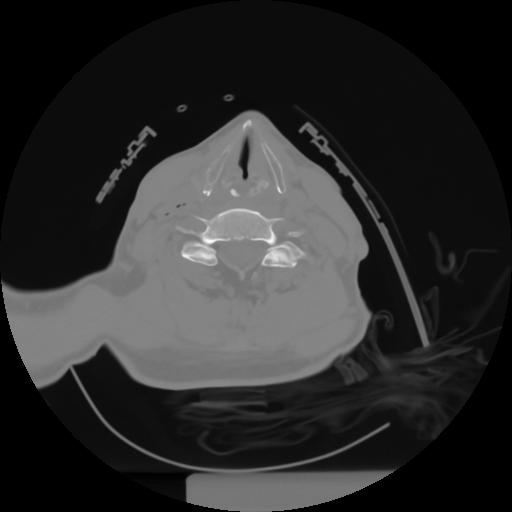

10 P.BLANDAS,,Axial,2.0,P.BLANDAS,,